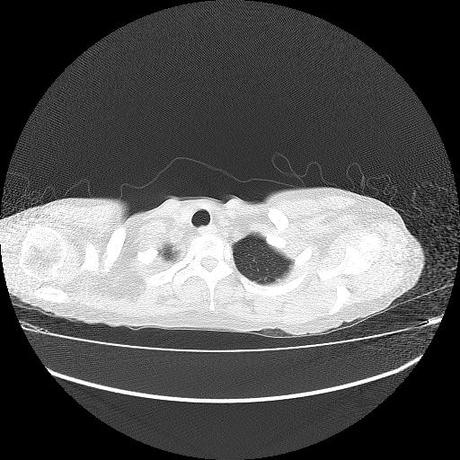

Se realiza volumen de tórax en fase simple, desde los opérculos torácicos hasta los hemidiafragmas, observándose:

El parénquima pulmonar con areas parcheadas difusas en vidrio despulido combinadas con otras areas hipodensas de baja atenuación debidas a atrapamiento aéreo y engrosamiento intersticial y zonas de fibrosis de predominio en lóbulos medios e inferiores de ambos pulmones.

La pleura se encuentra conservada, sin engrosamientos.